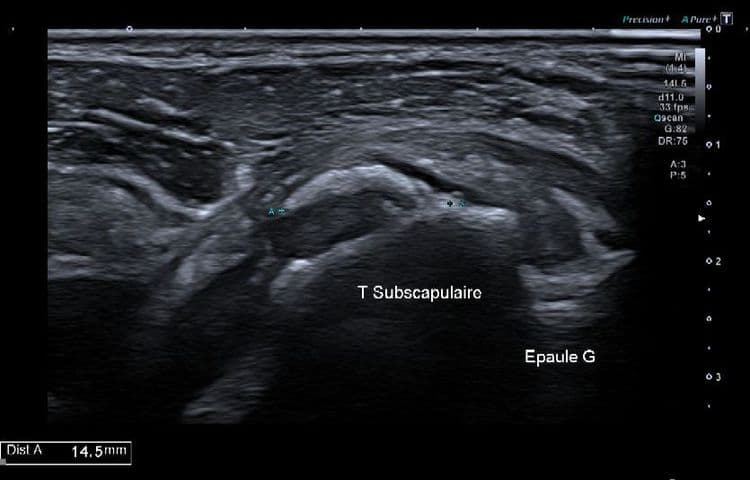

Cas d'une résorption calcique aigue du tendon sous-scapulaire

US